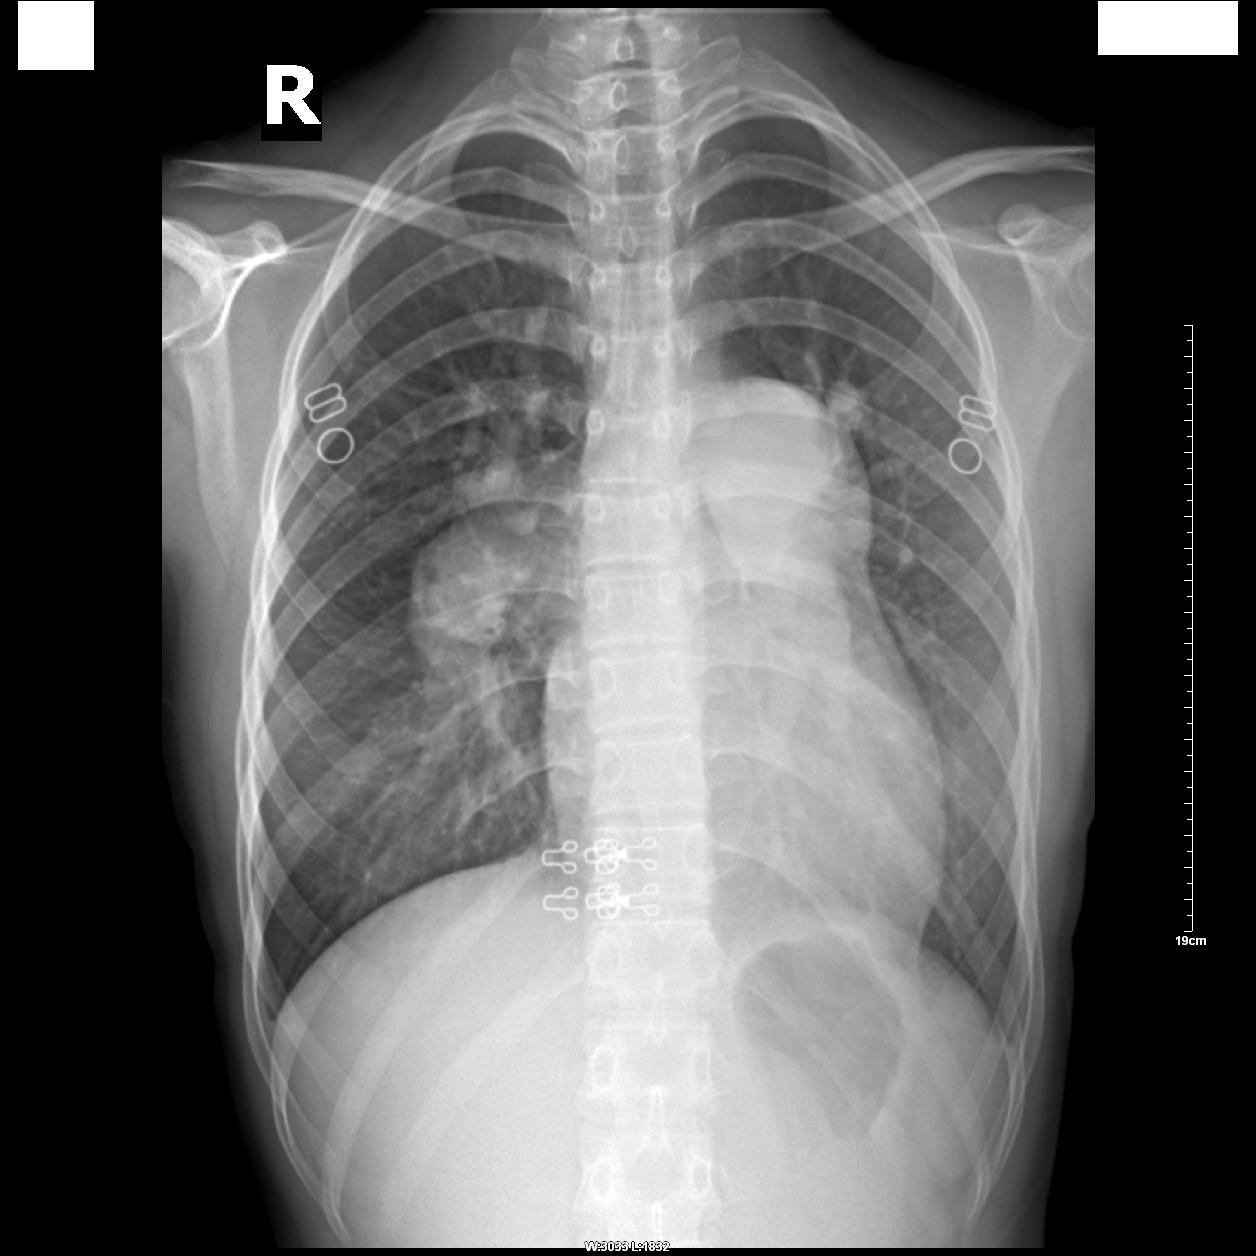

患者,女,18岁,气喘、紫绀多年!

心影呈“二尖瓣型”,肺动脉段瘤样凸出,肺门动脉明显扩张,外围分支变细、扭曲、稀疏,呈“残根状”,两上肺静脉略扩张,主动脉结缩小。

真可惜!这么年轻就已经出现右向左分流及严重的肺动脉高压,失去了手术机会!